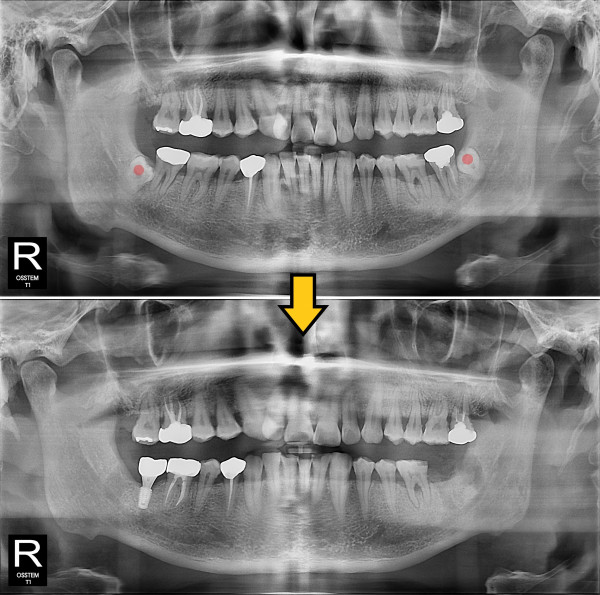

사랑니발치 완전 매복 사랑니

ae27575af29d49719312fde5a1f0cca6_1764401898_7411.jpg